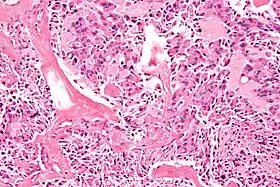

![]() صورة مجهرية لسرطان الغدة الدرقية اللبيّ والذي قد يظهر في MEN 2A و MEN 2B. صبغة الهيماتوكسيلين واليوزين صورة مجهرية لسرطان الغدة الدرقية اللبيّ والذي قد يظهر في MEN 2A و MEN 2B. صبغة الهيماتوكسيلين واليوزين | |